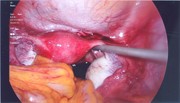

Laparo-endoscopic combined approach for excision of gastrointestinal stromal tumour close to the oesophagogastric junction

Zak Vinnicombe and others

Journal of Surgical Case Reports, Volume 2015, Issue 7, July 2015, rjv079, https://doi.org/10.1093/jscr/rjv079